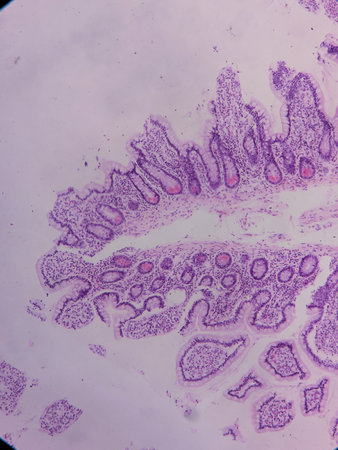

Small intestine with villi under the microscope 100x